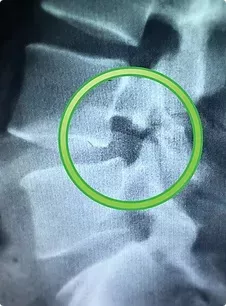

1. Функциональная спондилография - рентген в положении максимального поясничного сгибания и разгибания (важно максимально исключить движения в тазобедренных суставах). При проведении данного исследования можно определить дополнительное патологическое смещение вышележащего позвонка. При проведении спондилографии также возможно выявить спондилолиз - структурный дефект межсуставной части дужки позвонка.

Рентген поясничного отдела позвоночника. Показан спондилолиз - структурный дефект межсуставной части дужки позвонка.